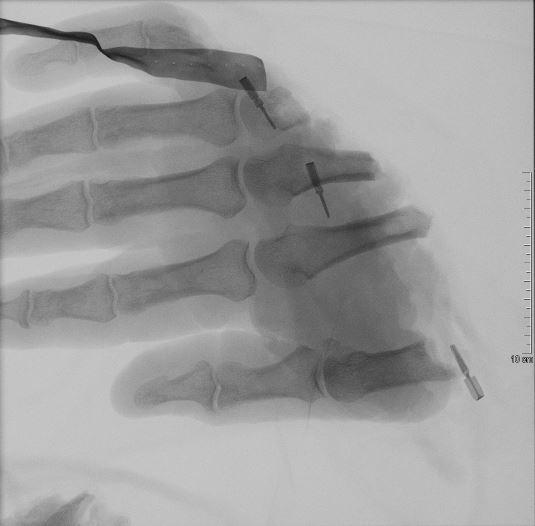

MehrReplantation – Abgetrennte Hand erfolgreich angenäht

Erneut wurde im BundeswehrZentralkrankenhaus (BwZKrhs) Koblenz eine abgetrennte Hand erfolgreich replantiert.